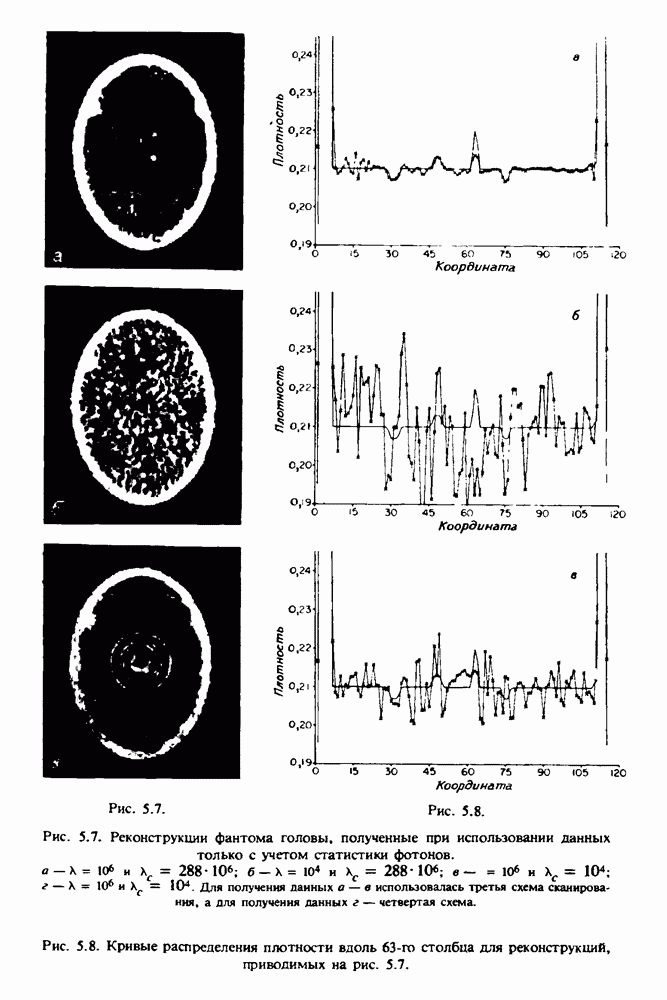

15.5. ЭКСПЕРИМЕНТАЛЬНЫЕ РЕЗУЛЬТАТЫ

Наш первый пример относится к случаю отображения системы желудочков головного мозга человека, которое было сделано по восьми смежным срезам толщиной На рис. 15.1 (вверху) приведены фрагменты из 80 х 80 элементов изображения трех из указанных срезов. Система желудочков изображена на фрагментах полностью. Размер элемента изображения в срезах составлял 1,5 х 1,5 мм, что соответствовало размеру элементарного

объема 1,5 х 1,5 х 8 мм, хотя более желательна, как и в предыдущих разделах, была бы кубическая форма элементарных объемов. Чтобы преобразовать элементарные объемы в кубические, использовалась линейная интерполяция данных для оценки 38 смежных срезов толщиной 1,5 мм. Таким образом, формируется массив из 80 х 80 х 32 чисел, характеризующих среднюю плотность множества элементарных объемов кубической формы.

Причина, по которой желудочки мозга выглядят более темными, чем окружающие ткани, состоит в том, что они содержат спинномозговую жидкость с несколько меньшим, чем у мозга, линейным коэффициентом ослабления (табл. 4.1). Поэтому диапазон значений, введенный в разд. 15.1, оказался таким, что его верхний предел стал больше, чем линейный коэффициент ослабления цереброспинальной жидкости, но меньшим, чем для самого мозга. Последнее означает, что все элементарные объемы, характеризующие спинномозговую жидкость, имеют числа Хаунсфилда в указанном диапазоне Таким образом, множество элементарных объемов, в которых числа Хаунсфилда лежат в диапазоне (разд. 15.2), содержит не только области желудочков, но также и другие части мозга, либо заполненные спинномозговой жидкостью, либо не заполненные ей, но имеющие по разным причинам такие же числа Хаунсфилда в данном диапазоне, например, вследствие наличия шума в исходных данных, артефактов при реконструкции и т.д. Элементарные объемы, которые принадлежат множеству изображены в виде светлых областей в нижней части рис. 15.1. Анатомическая картина соответствующих частей системы желудочков, показывающая в том числе положение corpora quadragemina («четверохолмие»), приведена на рис. 15.6.

Рис. 15.6. Анатомическая структура фрагмента системы желудочков головного мозга человека. 1 — передние рога латерального желудочка; 2 — третий желудочек; 3 — четверохолмие; 4 — задние рога латерального желудочка.

Рис. 15.7. (см. скан) Трехмерные проекции зарегистрированной поверхности системы желудочков головного мозга человека.

Для формирования трехмерного изображения системы желудочков (рис. 15.7) были использованы все рассмотренные в трех предыдущих разделах операции определения границ органов, исключения скрытых их частей поверхности и наложения теней. Число зарегистрированных граничных граней для системы желудочков составляло 8970, при этом регистрация множества из 80 х 80 х 38 элементарных объемов требует менее 0,5 мин машинного времени (на мини-ЭВМ типа Eclipse S/200).